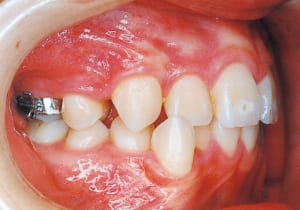

14 After extraction of maxillary bilateral first premolars 11-6-’90

15 At second stage treatment initiation 9-21-’91 Observing eruption of maxillary canines

16 Four months post-second stage treatment initiation 2-29-’92 Currently using headgear on maxill

17 At start of full bracket treatment 5-18-’92

In the maxilla, insufficient space for canine eruption was inevitable, necessitating extraction as part of the treatment plan. The maxillary first premolars on both sides were extracted during routine observation to create space for canine eruption (14). Eventually, the canines erupted and settled into relatively favorable positions (15,19,20). In the mandibular dentition, crowding was also present, leading to extraction of the mandibular first premolars on both sides. Treatment with full bracket was then initiated (17).